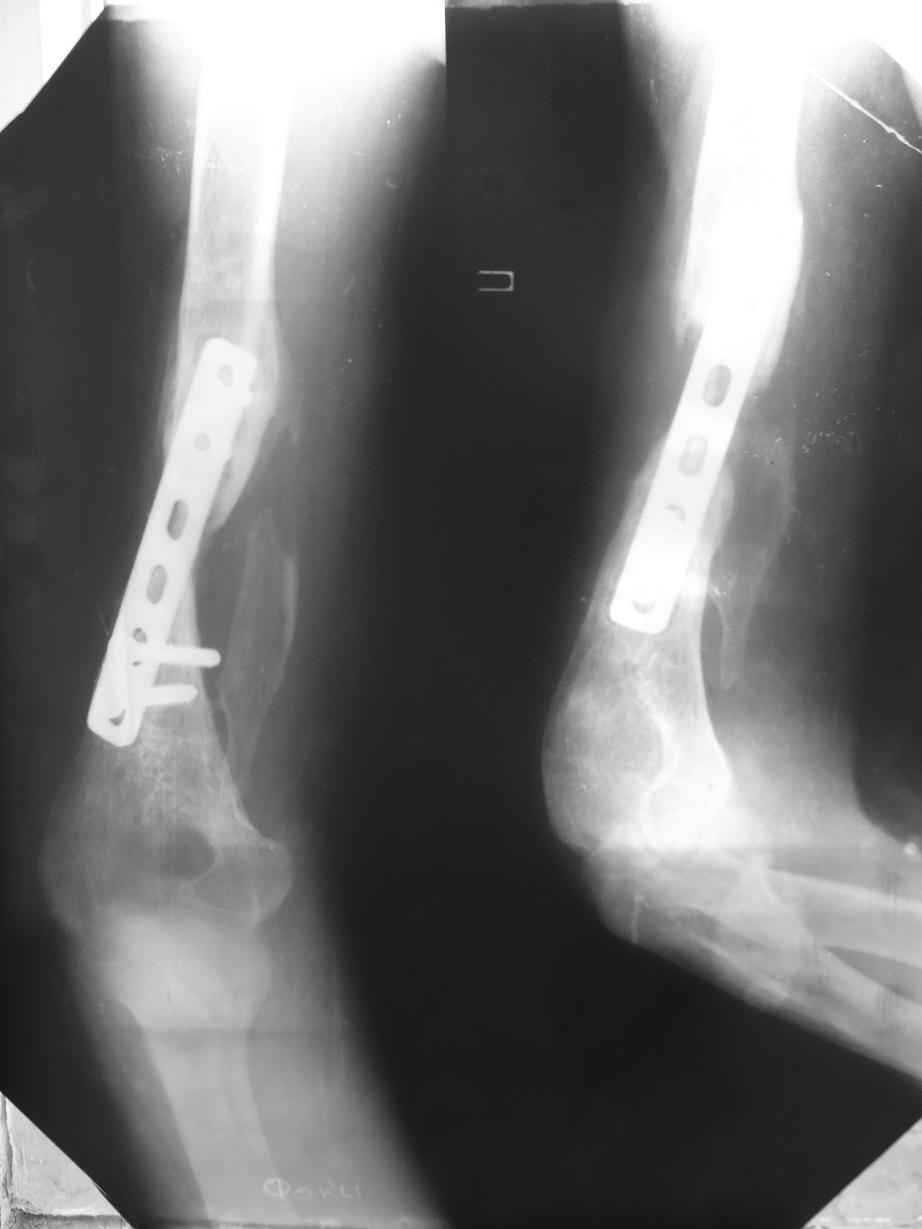

Поступил больной с ложным суставом плечевой кости...

Перелом был 2 года назад. Лечился в аппарате 8 месяцев, консолидации не

произошло. В феврале 2007 выполнена костная аутопластика, фиксация

пластиной (на базе одной из ИК). Сейчас сохраняется ложный сустав, плечо

укорочено на 3 см, контрактура обоих смежных суставов, атрофия мышц

плеча и плечевого пояса справа. Явлений остеомиелита не отмечалось.